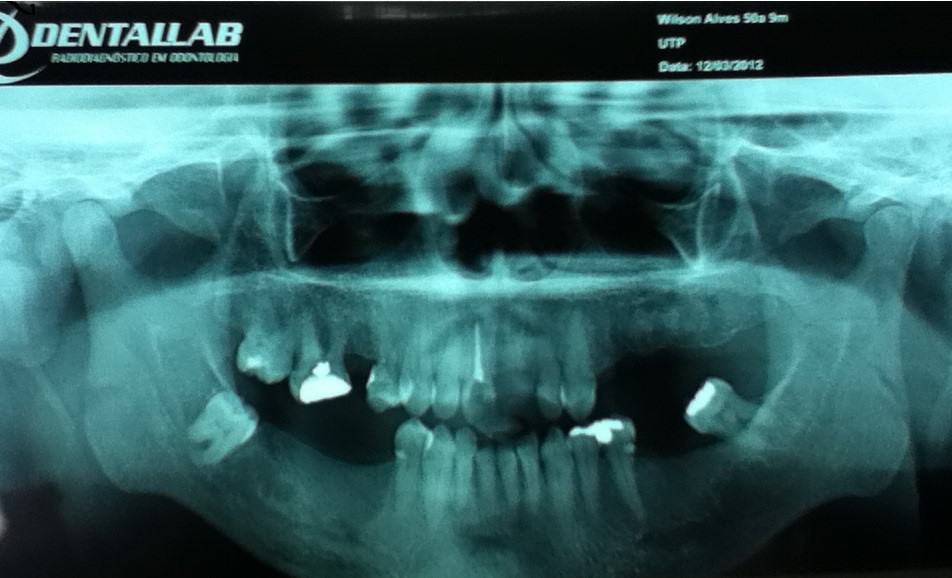

Paciente do sexo masculino, 51 anos, casado, negro, procurou a Universidade Tuiuti do Paraná, em 19 de fevereiro de 2013, para obturação do dente 11, queixando-se de um buraco na gengiva, em cima do elemento, por onde drenava grande quantidade de secreção purulenta.

Ao exame radiográfico, observou-se extensa área radiolúcidas, constatando uma fístula, lesão periapical envolvendo região periapical do referido dente.

- Figura 1 – Radiografia panorâmica.